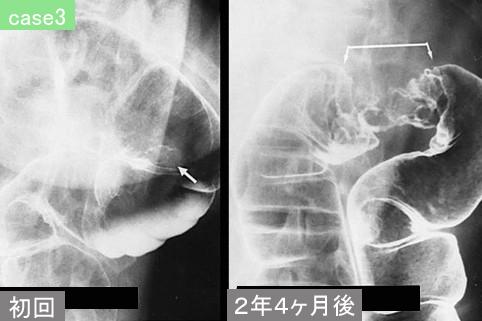

Five cases of advanced colorectal cancer in which two times barium enema examination were done by various reasons.

대장/하행

2형(궤양국한형)/

40이상

s(a)